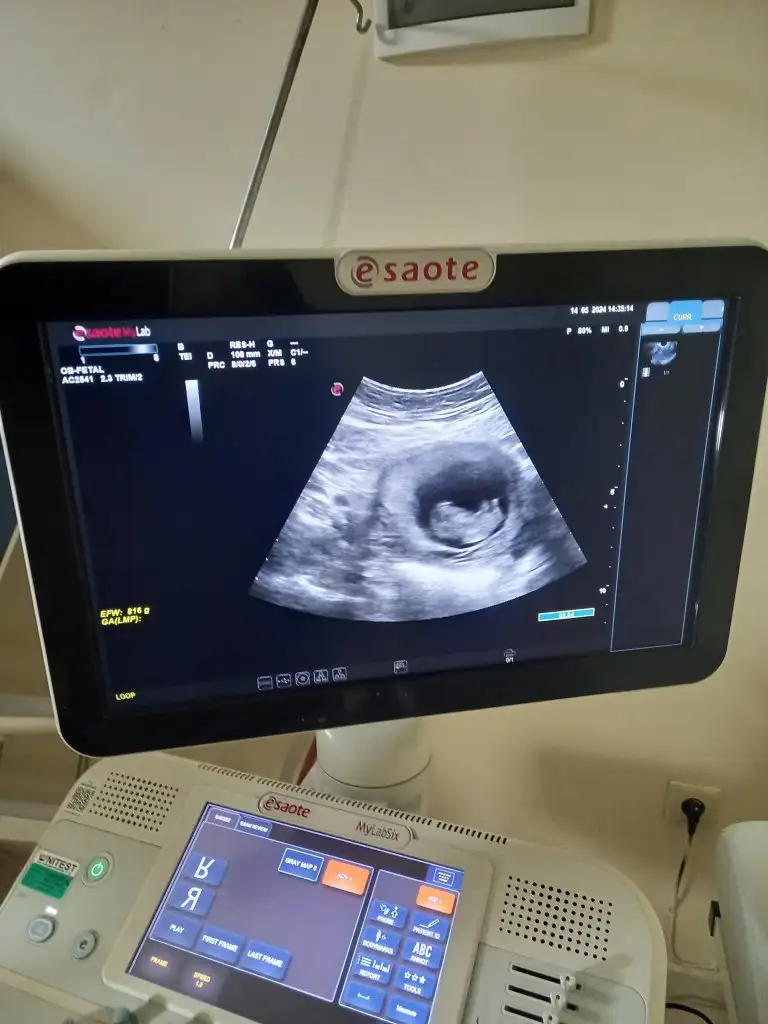

Küçük 6 haftalık var daha 11. Haftamıza girdik doktora gitmedik dahaBaşka görüntü var mı

Erkek olabilir belki çok emin olamadımKüçük 6 haftalık var daha 11. Haftamıza girdik doktora gitmedik daha

merhaba bana da bakabilir misin . karından . 10+1 . :)Kız gibi

Kız gibimerhaba bana da bakabilir misin . karından . 10+1 . :)